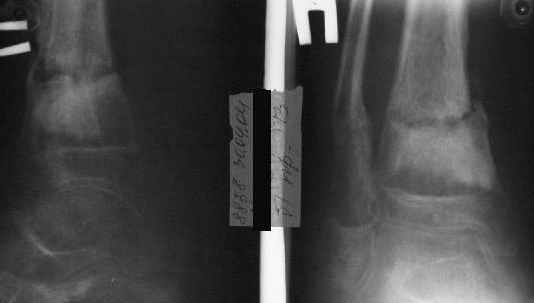

A>> Перелом костей н\3 правой голени со смещением.

AVM> Это от 13.10.04? А это близкие к первичным снимки?

Есть даже тень периостальной костной мозоли и сросшийся перелом

малоберцовой кости.

Первичные